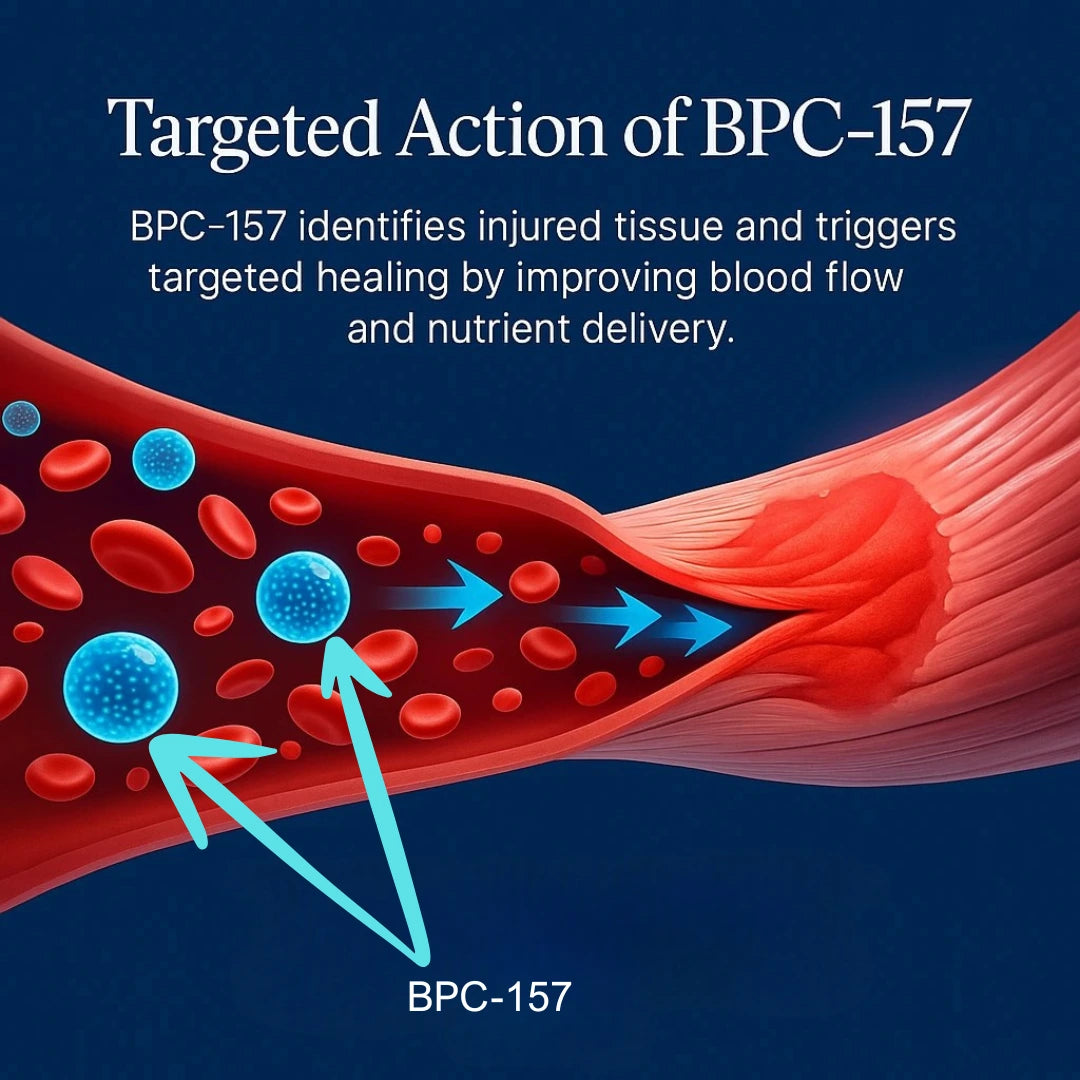

Step 2:

Targeted Action of BPC-157

BPC-157 identifies injured tissue and triggers targeted healing by improving blood flow and nutrient delivery.

5. How does BPC-157 actually work in the body?

5. How does BPC-157 actually work in the body?

BPC-157 is a peptide known to support tissue repair, blood flow, and inflammation modulation. It may help stimulate healing processes in muscles, tendons, joints, and even the digestive tract by interacting with growth and repair pathways.